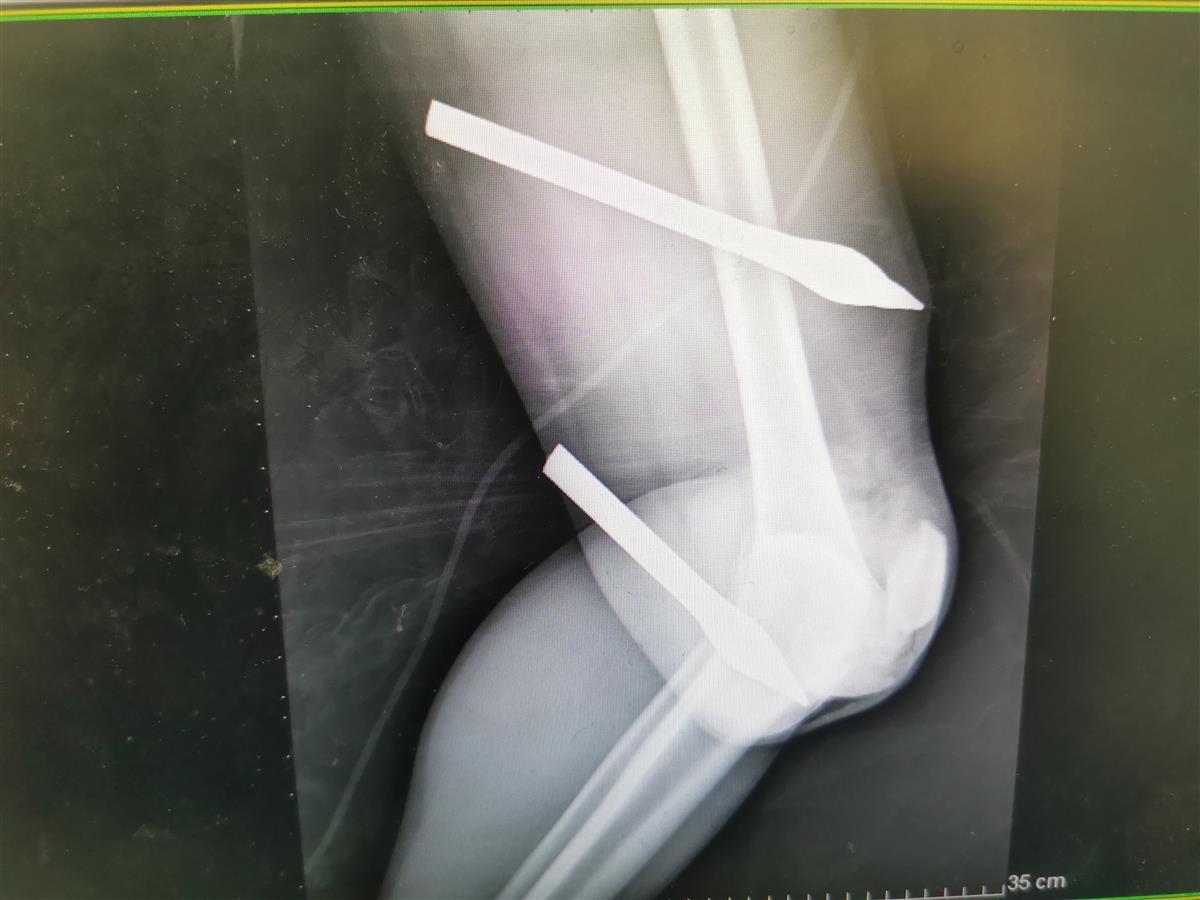

近日,44岁的李先生(化名)不慎从近15米高的阳台失足坠落,两根直径1公分、长近20厘米的钢筋分别贯穿大腿内侧与膝盖骨。幸运的是,钢筋与下肢大血管“擦肩而过”,经武汉市第五医院创伤外科中心多学科联合抢救后,李先生目前已经脱离生命危险,等候下一步治疗。

下午1时41分,院前120救护车将伤者到达武汉市第五医院。急诊科医护团队立即给予生命支持治疗,同步进行下肢CT床前检查,并立刻组织骨科、普外科、神经外科、泌尿外科等专家进行多学科会诊。完善检查后,初步诊断为左下肢金属贯穿伤、全身多处骨折、膝关节脱位等。严重的是,因膝关节脱位阻断了左下肢小腿血液循环,急需手术。

从影像结果来看,两根钢筋刺穿下肢

下午2时55分,患者被送入手术室,创伤外科中心医护立即到位,并迅速做好术前准备。麻醉师在超声引导下,精准放置深静脉导管并予以插管全麻,专家团队争分夺秒小心将钢筋从伤者下肢取出,避免造成二次伤害,并迅速行血管吻合术。下午4时50分,手术顺利完成,患者生命体征稳定,被送入骨科病房。